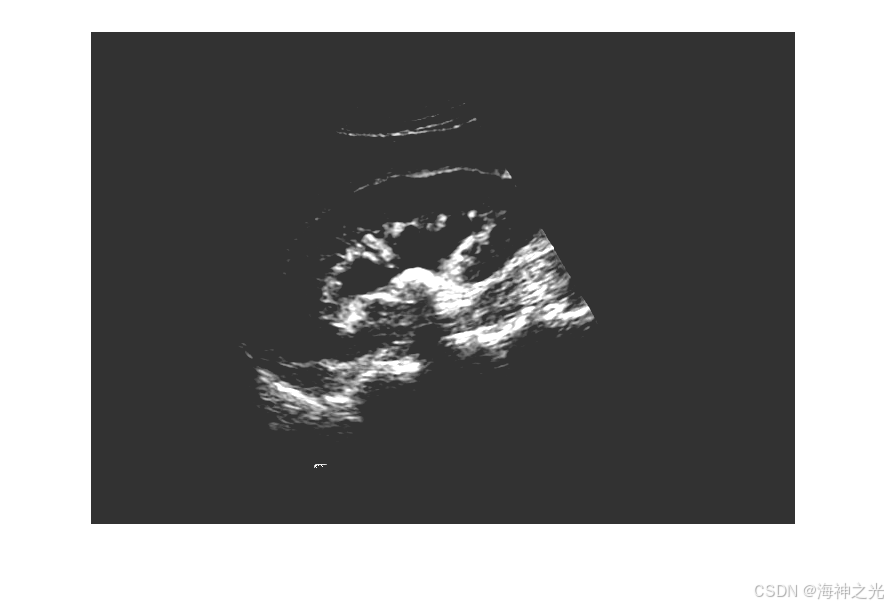

⛄三、运行结果